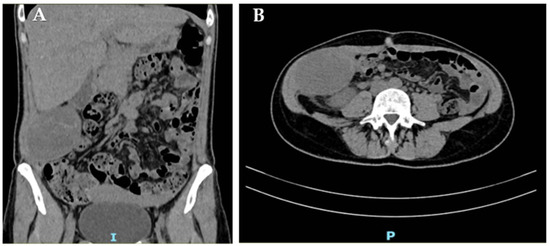

Follow-up MRI (May 2023) performed elsewhere revealed a solid, ovoid, hypointense nodule located between the right internal oblique and transversus abdominis muscles, described as consistent with fibrotic sequelae of endometriosis. Transabdominal US performed at our Clinic, confirmed a well-circumscribed, hypoechoic, moderately vascular lesion measuring 22 × 16 × 25 mm (Figure 1). Planned excision was postponed when the patient conceived again through IVF.

Figure 1.

Transabdominal US of the right abdominal wall: (A) measurements of the lesion and (B) its color-Doppler vascularization.